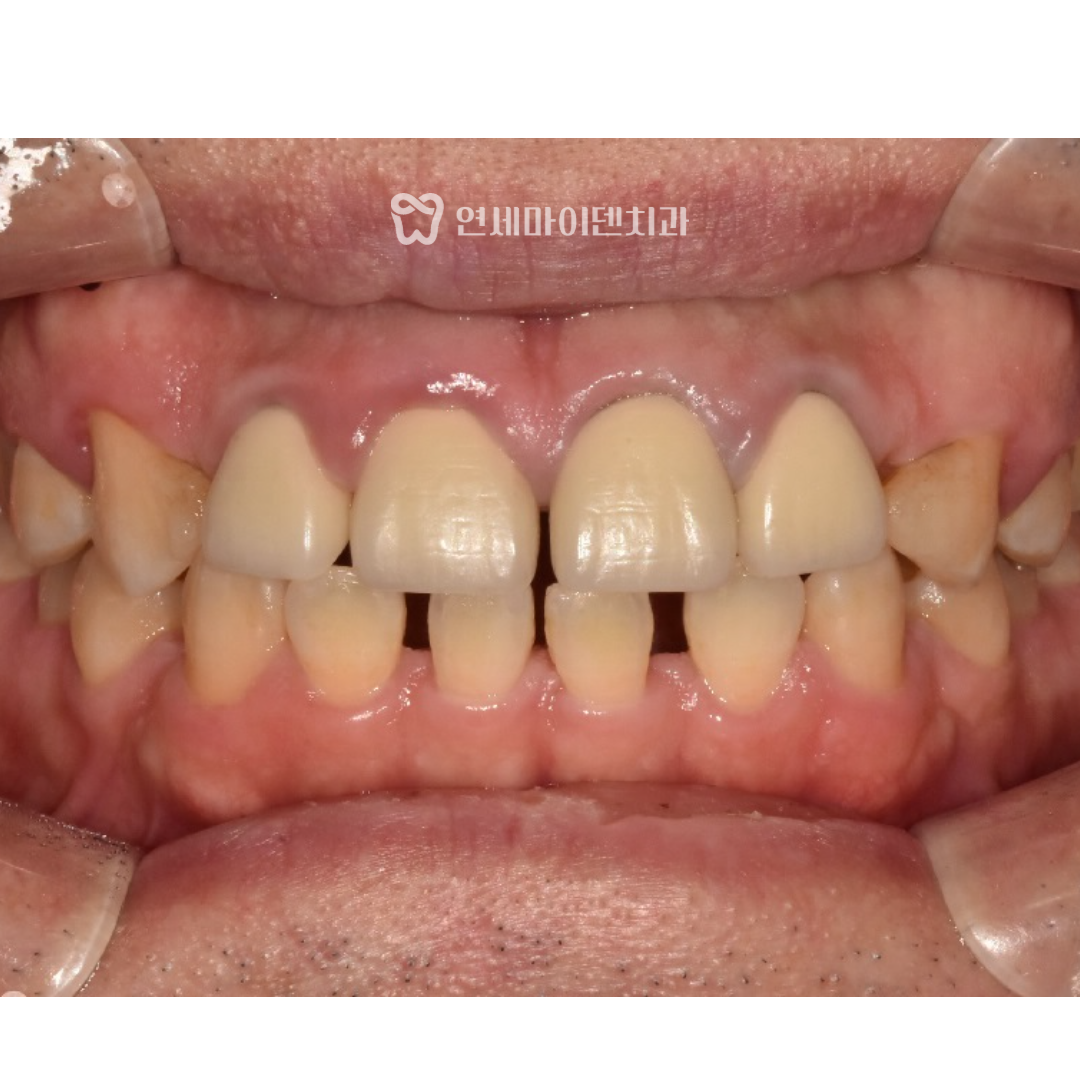

이 환자분은 앞니 사이 공간이 넓다는 주소로 내원하셨습니다.

위아래 앞니는 모두 벌어져 있었고,

인비절라인 교정 전에는 앞니 사이 공간이 넓고 배열이 불규칙하여

입술 돌출이 두드러졌지만,